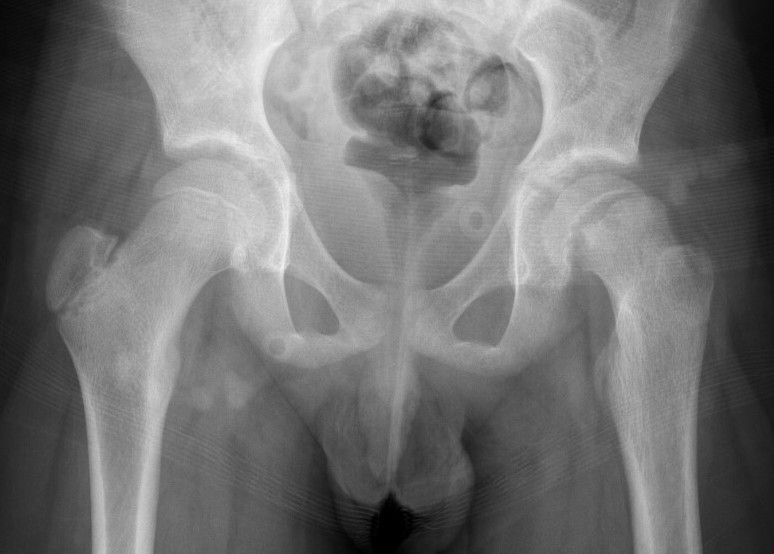

Lateral xray

Mild and moderate SCFE on left hips

Southwick classification

Southwick Angle / Slip Angle

- epiphyseal-diaphyseal angle on frog leg lateral

- mild <30°

- moderate 30- 50°

- severe >50°

Mild Moderate Severe